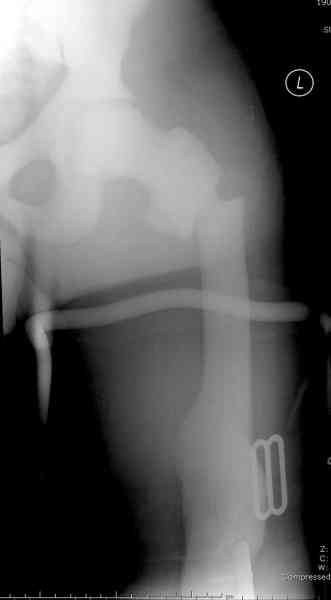

[2/3] Перелом проксимального бедра

Уважаемые коллеги, N2 ему 48 упал, перевели из другого учреждения на транспортном вытяжении,

10 лет назад лечился по поводу перелома дистального отдела бедра (снимки) и года два назад был перелом голени с этой же стороны. Подскажите вашу тактику.